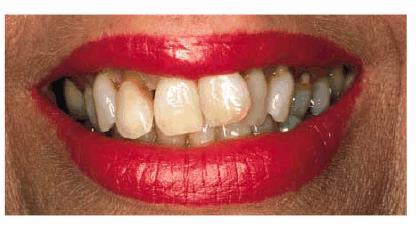

Figures 29-5A and B show a patient who did not like the

appearance of her front teeth. She felt that her maxillary central incisors

were too dark and too short. Cosmetic resin bonding was chosen as the treatment

of choice because of the immediacy of the result. Figures 29-5C and D show how the teeth were both lightened

and lengthened to provide a younger-looking smile line.

Figure 29-5A and B: This 78-year-old lady had shortened and darkened maxillary central incisors. (Reproduced with permission from Goldstein RE. Change your smile. 3rd edn. Carol Stream, IL: Quintessence, 1997:242.)

Figure 29-5C and D: Composite resin bonding was done to lengthen and lighten the central incisors. (Reproduced with permission from Goldstein RE. Change your smile. 3rd edn. Carol Stream, IL: Quintessence, 1997:242.)